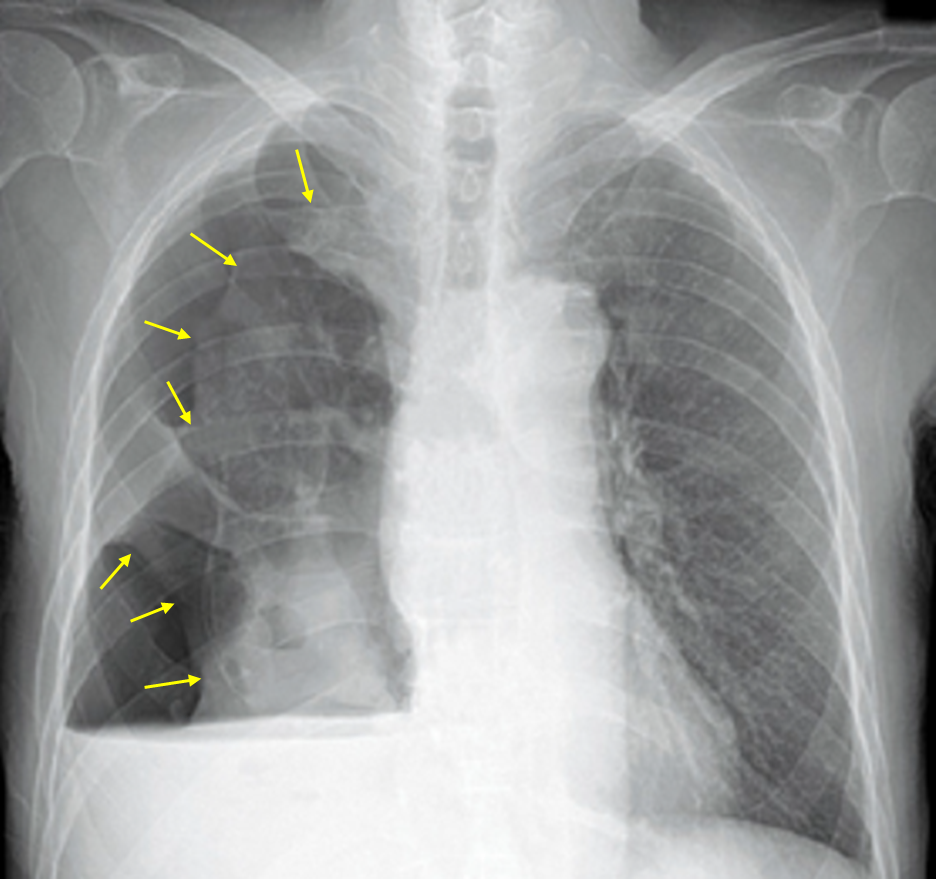

76세 남자가 1주 전부터 숨이 차고 가슴이 아파서 병원에 왔다. 3개월 전부터 기침, 누런 가래가 있었다. 1개월 동안 체중이 5kg 줄었고 기운이 없다고 한다. 30갑·년 과거 흡연자이다. 혈압 120/84mmHg, 맥박 98회/분, 호흡 20회/분, 체온 36.3℃이다. 오른쪽 아래 가슴에서 호흡음이 잘 들리지 않는다. 가슴 X선 사진이다. 혈액검사 결과는 다음과 같다. 진단은?

Img | CXR: 우측 폐 pleural line, air-fluid level |

• CXR에서 우측 폐에 pleural line이 보이며, air-fluid level이 보이므로 기흉과 흉막 삼출이 동시에 있음을 알 수 있다.

• 흉통과 호흡곤란은 기흉에 의한 것이라고 생각할 수 있다.

• 한편, 고령, 흡연력, 급격한 체중 감소에서 폐암이 의심되는데, 폐암으로 인한 이차성 기흉과 암성 흉수가 생긴 것으로 추측해볼 수 있다.